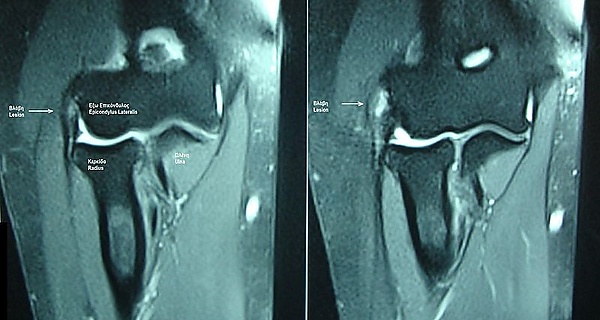

Магнитно-резонансная томография локтевого сустава показана для дифференциальной диагностики неясных случаев. В ходе исследования выявляют повышенную интенсивность сигнала в месте прикрепления сухожилия короткого лучевого разгибателя запястья, утолщение или дегенерацию сухожилия[12]. Самые характерные признаки латерального эпикондилита — утолщение и повышенная интенсивность сигнала в месте прикрепления сухожилия[13].